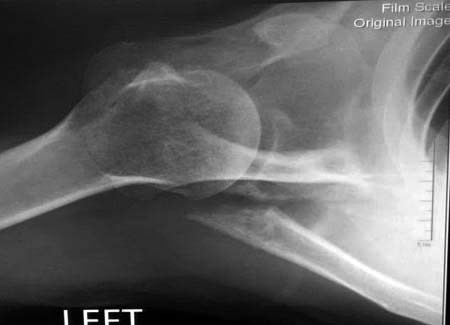

Данный перелом относится к перелому тело лопатки и несмотря на

наслоение, где лопатка покрывает грудную клетку, но можно увидеть три

большие фрагмента, которые находятся в разных плоскостях. Суставная

поверхность расположена намного медиальнее, что нарушает бланс мышц,

которая в последующем может привести к ограничению движения верхного

пояса. Расположение суставной поверхности нуждается в уточнении

дополнительными исследованиями, включая КТ и стандартные снимки плеча.!

Здесь пример, стандартные снимки: плечо и лопатка прямой снимок,

аксиллярный и косой снимки (Y-view) и фиксация пластинами по краям, где